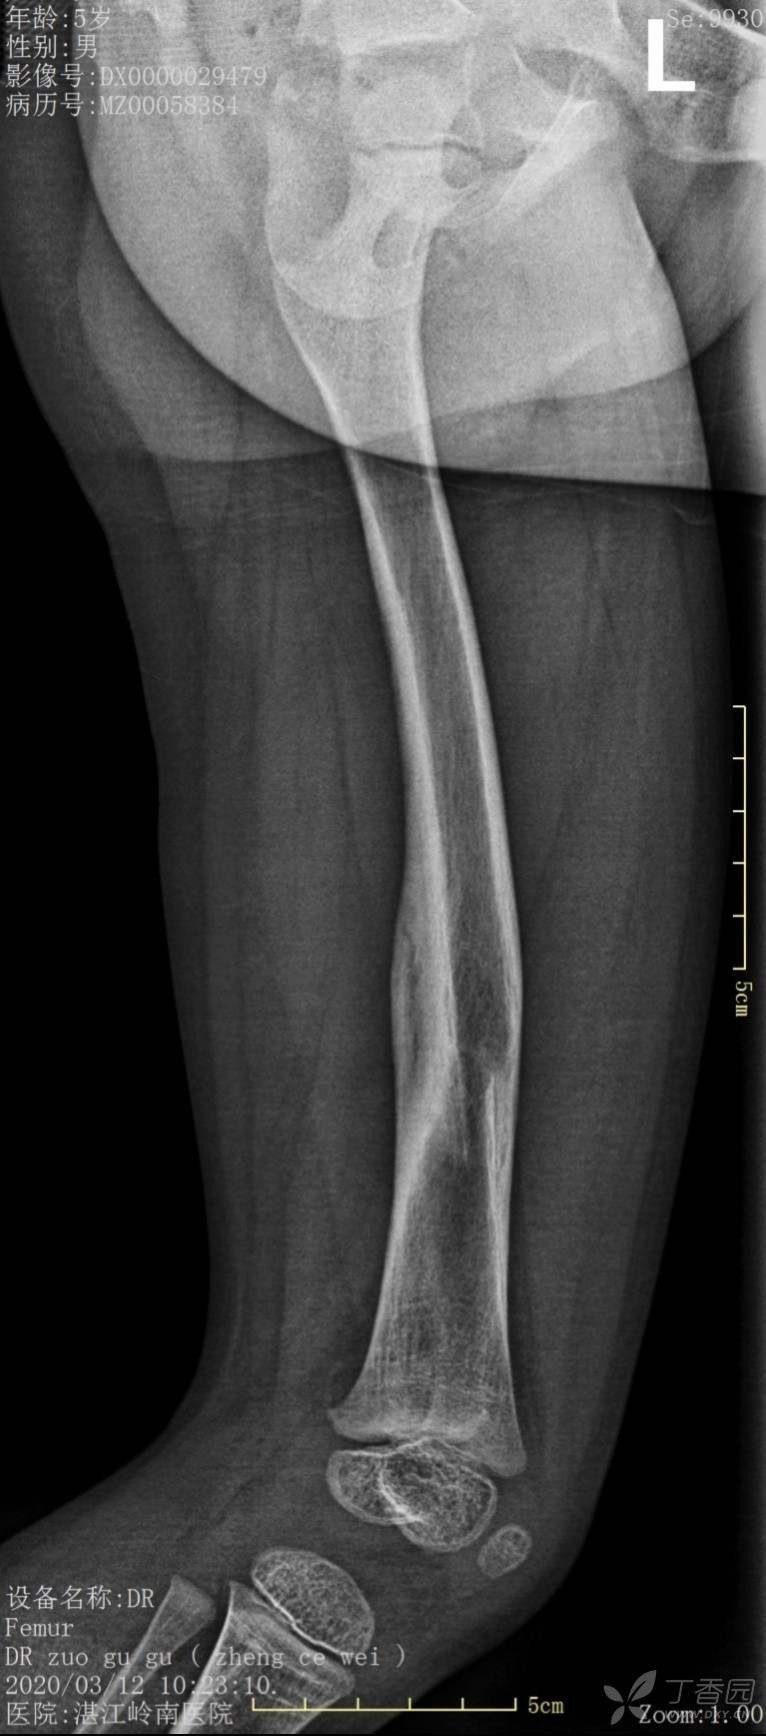

4岁患儿股骨骨折保守治疗一例

外伤时,保守1个月、2个月、6个月